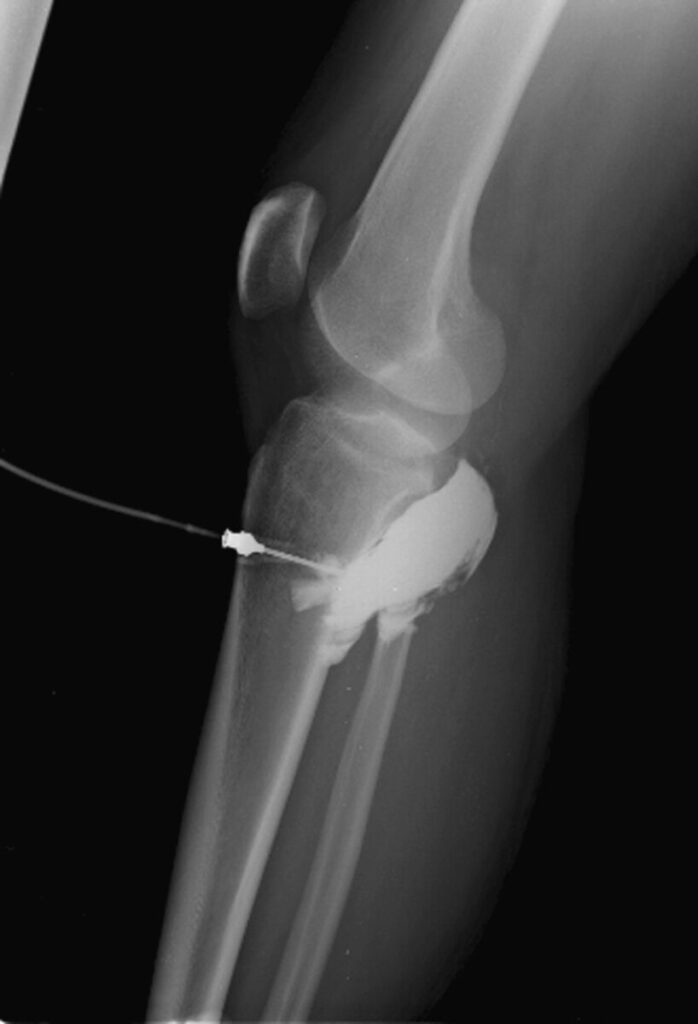

The PARAMEDIC-3 trial (Warwick) isn’t just clinical, it’s a cost-analysis study [1]. Crews drill an intraosseous gun into bone, pushing 1 mg adrenaline every 3–5 mins [2].